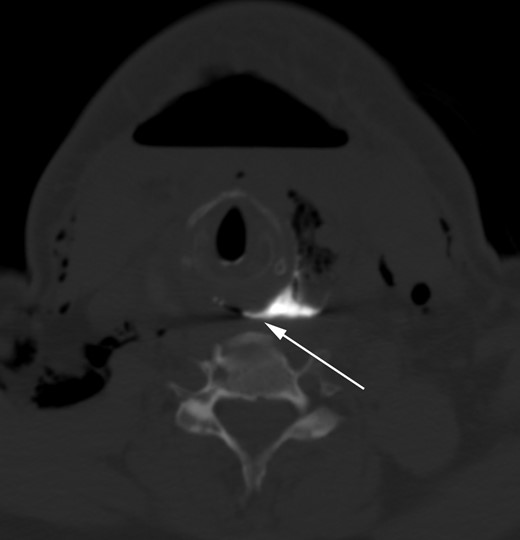

On the third postoperative day, however, the patient returned to the surgeon's office with complaints of neck pain and swelling. A CT scan of the neck performed at that time revealed a 7.7 × 3.7 cm fluid collection in the left neck (Fig. 1). The patient was taken emergently to the operating room, where upon opening the incision a large amount of purulent fluid was evacuated. There was a thick, yellowish exudate adherent to the involved surfaces, and the strap muscles were noted to be thickened, stiff and friable. Inspection of the esophagus revealed no obvious injury, but surrounding tissues were noted to be discolored and inflamed, making visualization of the esophagus difficult. The recurrent laryngeal nerve, which had been identified during the initial operation, was not seen.

Axial CT image of the neck without oral or intravenous contrast demonstrates an air fluid collection in the left thyroid lobectomy bed (white arrows). Subcutaneous emphysema and a large anterior neck air fluid collection (asterisks) are also present. T, residual right lobe of the thyroid.